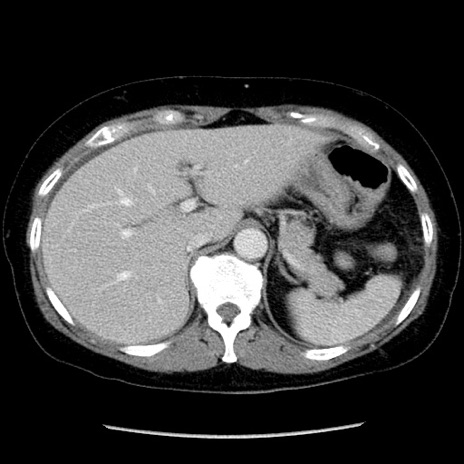

症例6(横断像)

【症例】50歳代女性

【主訴】下腹部痛

【現病歴】本日朝より下痢2回あり。 昼食を食べた後、嘔吐3回、下腹部痛認め、症状軽快せず、当院救急搬送。

最終食事:本日昼(生ものなし)。 昨日の夜、刺身を食ぺたとのこと。周囲に同様の症状の者なし。普段、排便は毎日あるとのこと。

【既往歴】卵巣癌術後(8年前に当院で卵巣摘出)

【身体所見】 意識清明、腹部:平坦、腸蠕動音→、やや硬、下腹部自発痛・圧痛あり、反跳痛あり、筋性防御なし。

【データ】WBC 16000、CRP 0.01